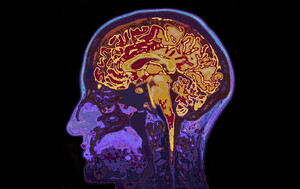

심정지 생존자의 뇌손상 영상 정확도는 촬영 시기 별로 다르다는 연구결과가 나왔다.충남대병원 응급의학과 민진홍·전소영 교수 연구팀은 심정지 후 발생하는 저산소허혈성 뇌손상(Hypoxic-Ischemic Brain Injury, HIBI)의 시간 별 진행 양상을 분석해 응급의학 분야 국제학술지(Resuscitation)에 발표했다.이번 연구 대상자는 심정지 생존자 122명. 이들을 심정지 후 6시간 이내(초기)와 72~96시간(아급성기) 두 시점에서 각각 뇌 MRI를 시행하고, 뇌속 물 분자의 확산 정도를 분석했다.연속 MRI 기반 겉

심정지 환자의 신경학적 경과 예측에 핵심인자가 처음으로 발견됐다.충남대병원 응급의학과 박정수, 강창신, 전소영 교수 연구팀은 심정지 환자의 혈중에 나타나는 두 가지 생화학 표지자(S100B 단백질, 뉴런 특이적 에놀라제[NSE])의 시간별 양상, 즉 '구획 간 동역학'(compartmental kinetics)이 경과 예측 정확도를 좌우한다고 중환자의학 분야 국제학술지(Critical Care)에 발표했다.기존에는 이들 표지자의 예측 정확도가 분자량의 크기나 혈액-뇌 장벽(BBB)의 손상 정도에 따라 달라지는 것으로 알려져 있었다.

급성심정지에서 회복 후 이차 뇌손상을 막기 위해서는 뇌세포의 대사속도를 낮추는 목표체온치료가 필요하다. 최근에는 급성심정지환자 이송 중에도 효과적이라는 연구결과가 나왔다.서울대병원 응급의학과 노영선·김기홍 교수팀은 이송 중인 급성심정지환자에 목표체욘치료를 적용한 결과, 환자의 체온을 13배 낮춰준다고 응급의료분야 국제학술지(Prehospital Emergency Care)에 발표했다.국내 급성심장정지 환자 발생수는 연간 약 3만명에 이르며 생존해 퇴원하는 환자가 10명 중 1명도 되지 않는다. 응급 소생술로 심장박동이 정상 회복돼도

혈액지표를 이용해 심정지환자의 회복 여부를 판단할 수 있다는 연구결과가 나왔다.가톨릭대 서울성모병원 응급의학과 윤준성(교신저자)·성빈센트병원 응급의학과 송 환(제1저자) 교수팀은 심정지 후 혼수상태의 환자를 대상으로 회복 여부를 가늠하는 바이오마커(혈청지표)를 발견했다고 응급의학 국제학술지(Critical Care)에 발표했다.최근 심폐소생술의 활성화와 심정지 후 신경과 뇌 손상을 최소화하는 목표체온조절 치료가 확대 되면서 심정지 환자의 생존율도 높아지고 있다. 하지만 의료진이 심정지 후 혼수상태인 환자가 다시 정상으로 깨어날 수